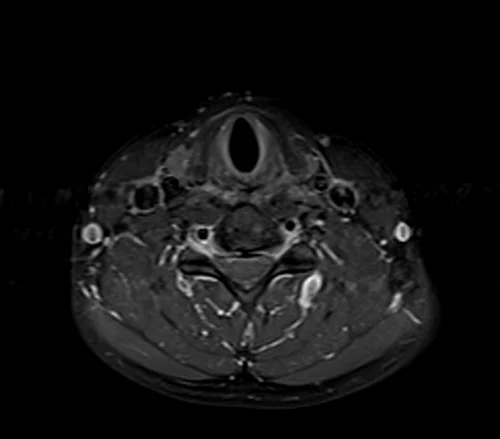

MRI Soft tissue neck axial T1 fat sat post contrast images